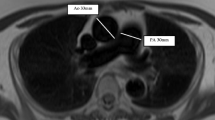

MR images were manually analysed by DC (a cardiac MRI radiographer of 9 years cardiac MRI experience) on a GE Advantage Workstation 4.4 and GE Advantage Workstation ReportCard software, with the observer blinded to all clinical information and other investigations. Left and right ventricular end-diastolic volume, end-systolic volume, right and left ventricular stroke volume and mass were calculated (all indexed to body surface area), right and left ventricular ejection fraction, ventricular mass index (RV mass divided by LV mass) [20] and interventricular septal angle were measured as previously described [15]. Right and left ventricular ejection fractions were calculated as (end diastolic volume minus end-systolic volume) divided by end diastolic volume. Maximal and minimal PA areas were manually traced, and relative area change was defined by the following equation: RAC= (maximum area-minimum area/minimum area) [21]. Reproducibility metrics for these cardiac MRI metrics for DC and AJS have been previously published [22]. Please see Fig. 1 for a diagram of the key imaging metrics that were measured.

Diagram showing the methodology of calculation of the cardiac MRI metrics. Pulmonary artery relative area change (a) taken from cine images taken at the level of the pulmonary trunk, perpendicular to the main pulmonary artery; septal angle (b) taken as the angle made between the insertion points of the RV to the mid septum on the end-systolic image from the short axis stack; and (c) ventricular mass index taken by segmentation of the muscle mass of the left and right ventricle on the stack of images taken in the short axis plane